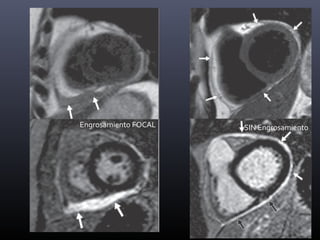

PERICARDITIS AGUDA

Pericarditis no es sinónimo de

engrosamiento

Engrosamiento DIFUSO

Engrosamiento FOCAL SIN Engrosamiento

ENGROSAMIENTO +

IRREGULAR

DERRAME

PLEURAL

VARIABLE

REALCE +

AFECTACIÓN

VENTRICULAR

-

PERICARDITIS

CRÓNICA

INFLAMATORIA